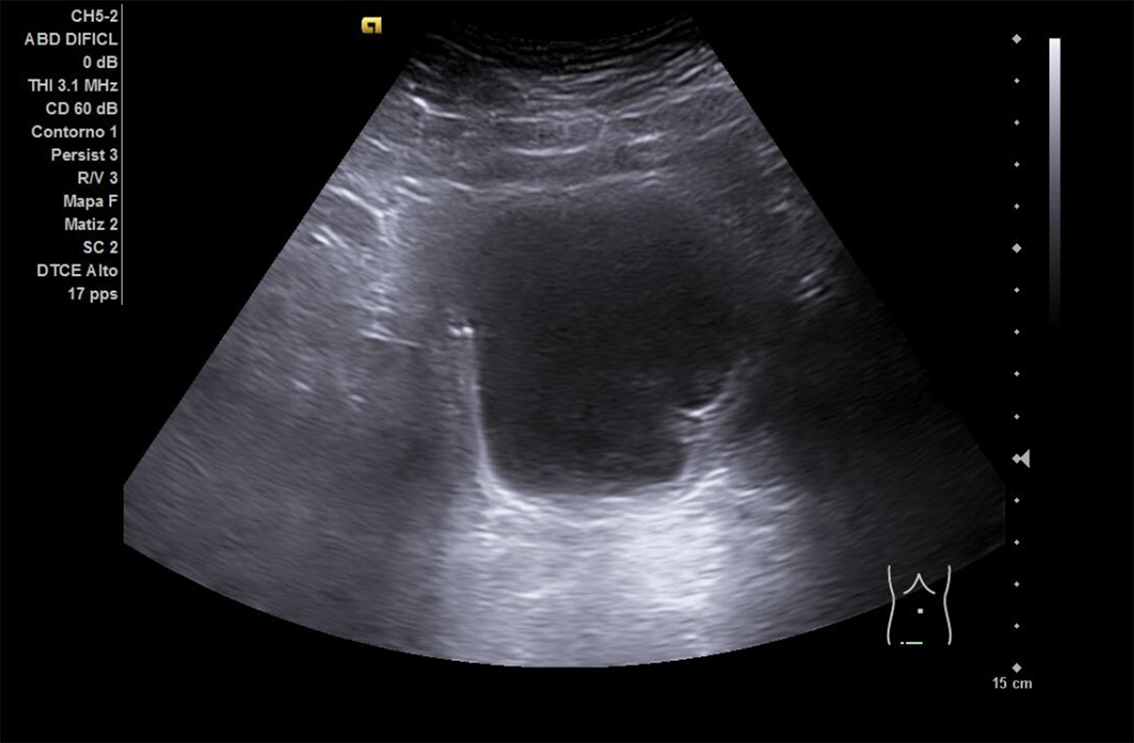

Se realiza ECO POCUS en la que se aprecia riñón derecho de morfología y tamaño normal. Riñón izquierdo con hidronefrosis grado III. A nivel de vejiga, bien replecionada se aprecia masa a nivel de pared izquierda adyacente a unión ureterovesical de 1.8 x 2,7 cm Ausencia de jet izquierdo.